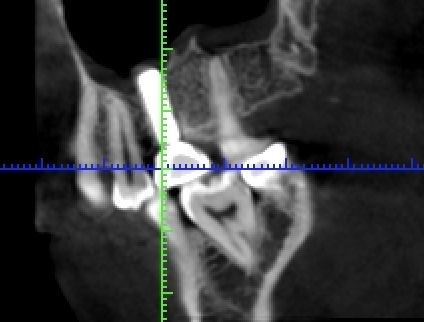

写真は同一部位のレントゲン写真とCT画像です。レントゲン写真は顎骨の形態や走行する神経の位置、歯が生えている方向把握することはできても2次元的な位置関係でしか把握できません。つまり歯や神経の位置がわかっていても実際にどのくらいの位置関係にあるのかを正確に判断することはレントゲン写真では不可能なわけです。しかし、歯科用CT画像では顎骨の形態や走行する神経の位置、歯の生えている方向、さらには骨密度の状態を3次元的に画像化する事が可能なため、より正確な診断する事ができます。

インプラント治療においてインプラントを埋入する部位の骨の状態を正確に判断することは非常に大事です。骨の厚み、形態、高さ、骨の内部に存在する血管や神経の走行を事前に確認しておく事でより安心安全にインプラント治療を行うためにCT撮影を行うことはインプラント治療において必須だと言っても過言ではありません。